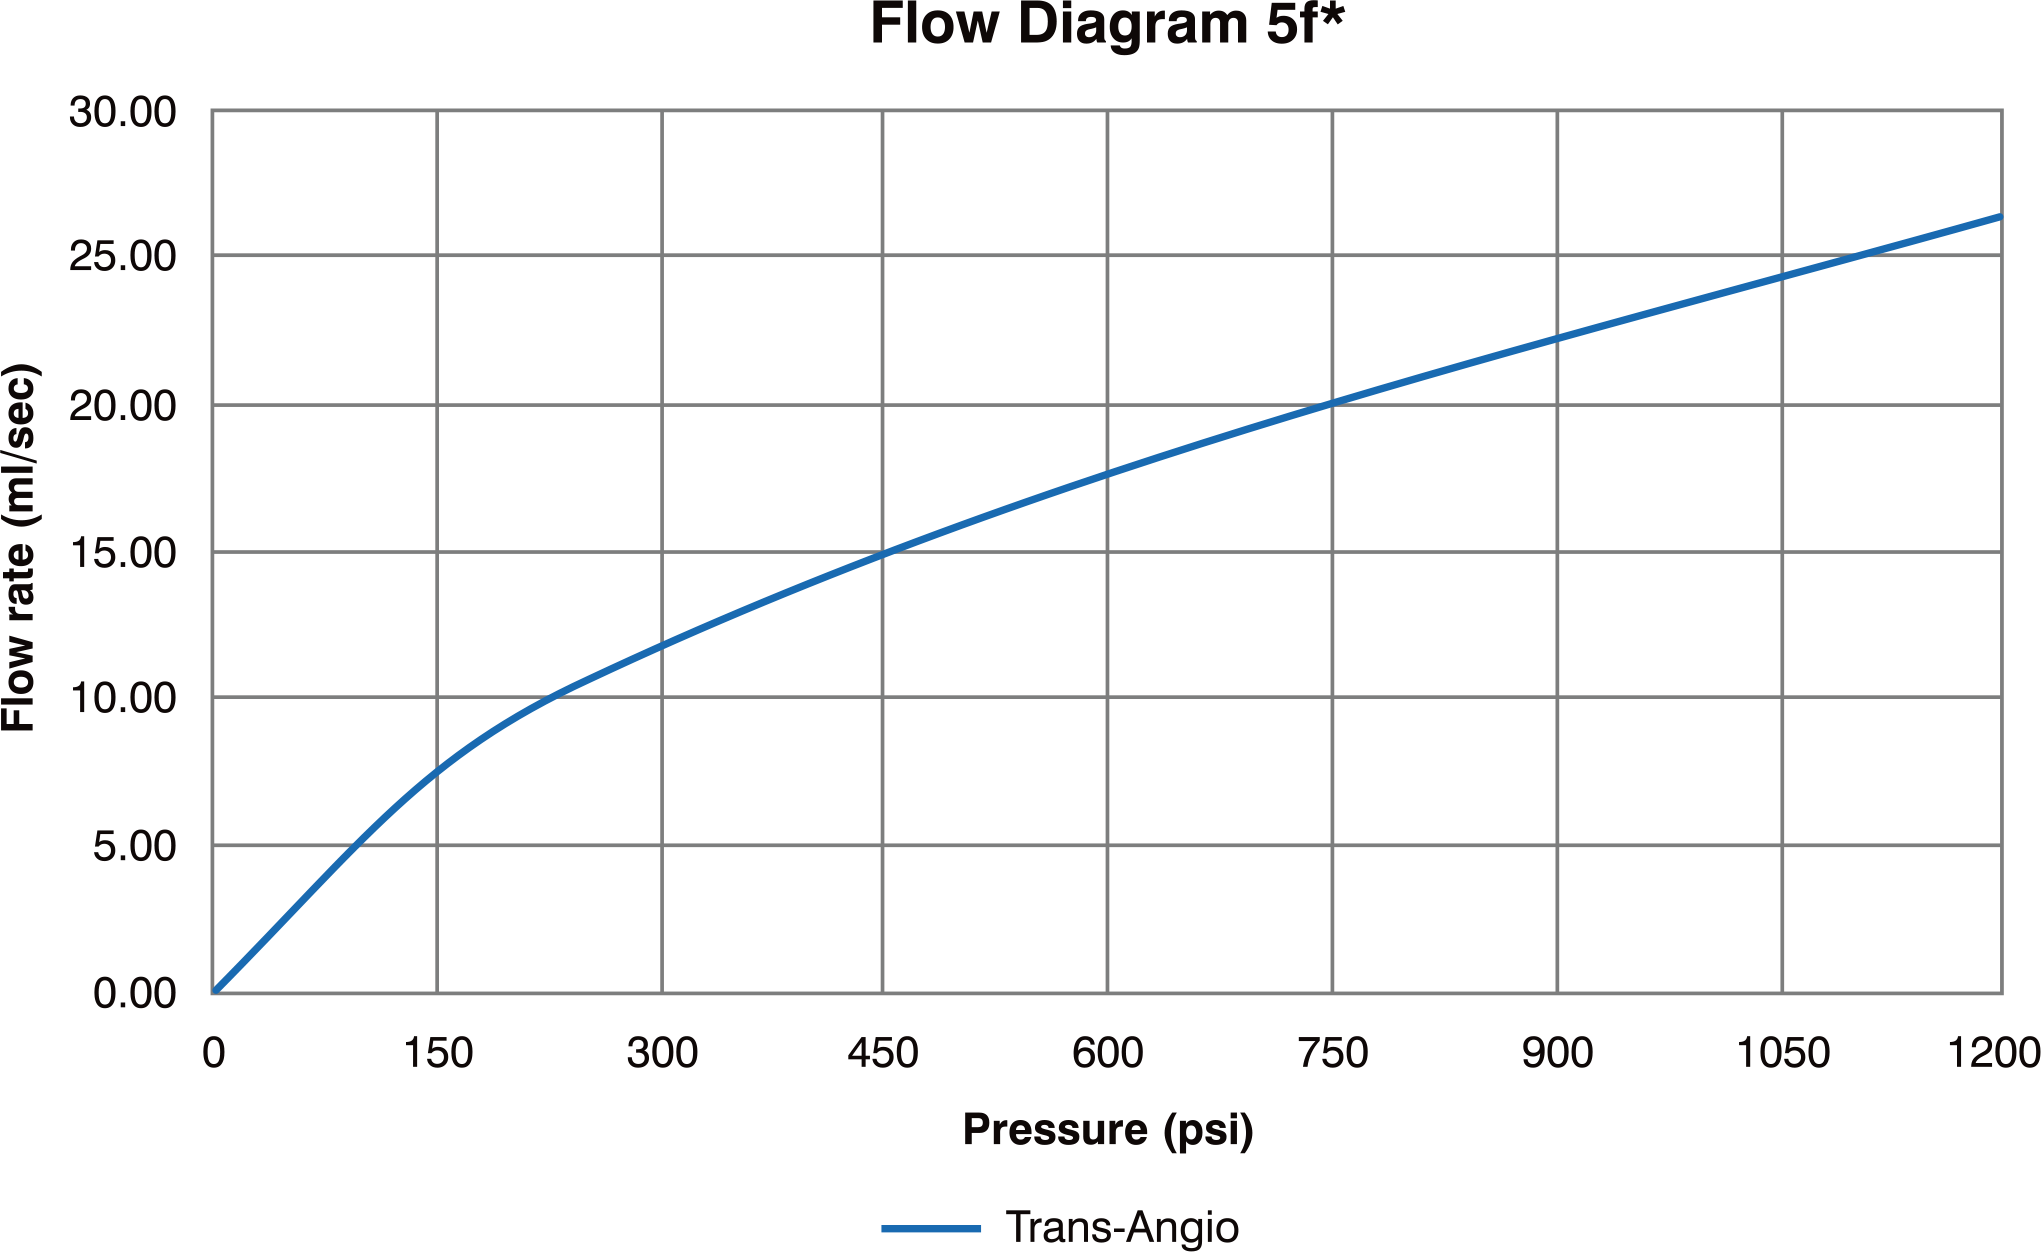

Radial Diagnostic Catheter

Features & Benefits

-

Enables angiography of both RCA and LCA with one catheter that can potentially:

• Eliminates a catheter exchange step

• Shorten procedure & fluoroscopic time

• Lower cost per procedure - Engages with simple clockwise & counter clockwise rotation

- Soft tip reduces potential for vessel trauma

- High Flexibility

- Superior Surface Smoothness

- Excellent 1:1 Torque Control due to double wire stainless steel braiding

- Large inner lumen for superior flow rates

- Atraumatic soft tip

- Guidewire Compatibility : 0.038”/ 0.97mm

- Max Pressure : 1200 PSI / 84 bar